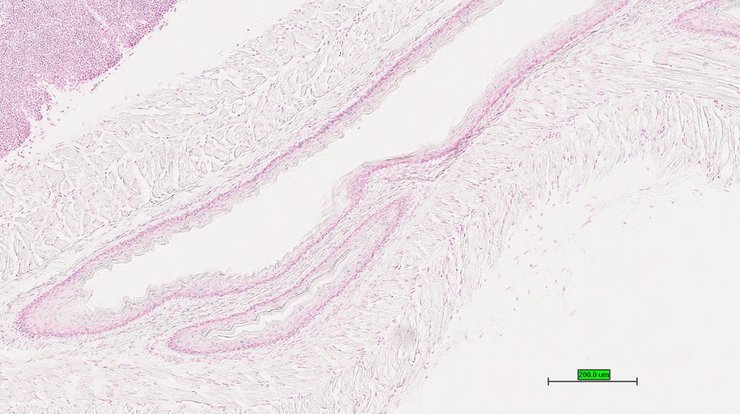

TS28: esophagus Present UC Davis_1876894

Specimen UC Davis_1876895: postnatal adult; Fosbtm1b(KOMP)Wtsi/Fosb+ (more )

Structure Level Pattern Image Note

TS28: esophagus Present UC Davis_1876895

Specimen UC Davis_1876896: postnatal adult; Fosbtm1b(KOMP)Wtsi/Fosb+ (more )

TS28: esophagus Present UC Davis_1876896

Specimen UC Davis_1876897: postnatal adult; Fosbtm1b(KOMP)Wtsi/Fosb+ (more )

TS28: esophagus Present UC Davis_1876897

TS28: esophagus Present UC Davis_1876911

Specimen UC Davis_1876912: postnatal adult; Fosbtm1b(KOMP)Wtsi/Fosb+ (more )

TS28: esophagus Present UC Davis_1876912